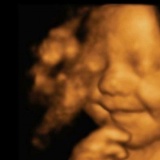

Ұлыбританияда тұратын Лео есімді әлемдегі ең күлегеш сәбидің ата-анасының айтуынша, ол қашан көрсең де ұдайы күлімсірейді екен. Яғни, езуі бір жиылмайды. Ол ол ма, ол анасының құрсағында жатқанда да күлімсіреген көрінеді. Тіпті оның күлімсіреген жүзі 4D-УЗИ-ге түсіп қалған.

Жас жұбайлар Эми Крэг и Лейтон Харгривз болашақ сәбилерінің жүктіліктің 31-ші апталығында күле бастағанын жайып салды. Дәрігерлер сәбидің бұл қылығынан қандай да бір қауіп көріп тұрған жоқ. Қайта жағымды жаңалыққа балап отыр: өмірге келген алғашқы күнінен бастап, шуақты әрі шат күлкісімен ата-анасын қуантқан сәбидің дұрыс бағытта өсіп-жетіліп келе жатқанын айтқан. Сәби, тіпті, ұйықтап жатқанда да күлімсірейтін көрінеді. Сәбиге сән агенттіктері өз жарнамаларында пайдалану үшін оған «құда» түскен екен. Алайда, анасы оның әлі кішкентай екенін алға тартып, келісімін бермепті.